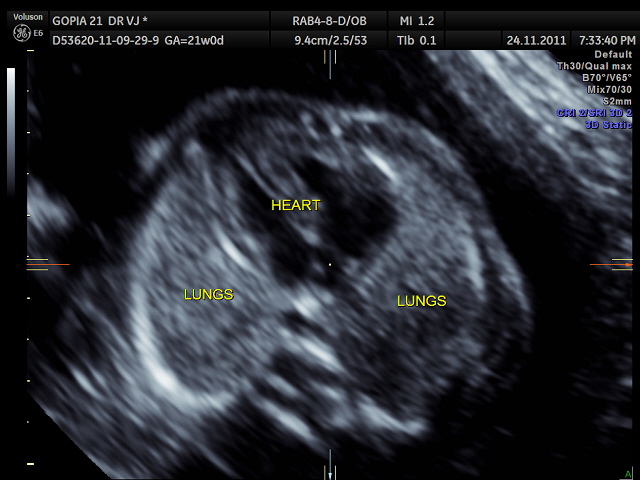

the following two pictures establish the normal situs